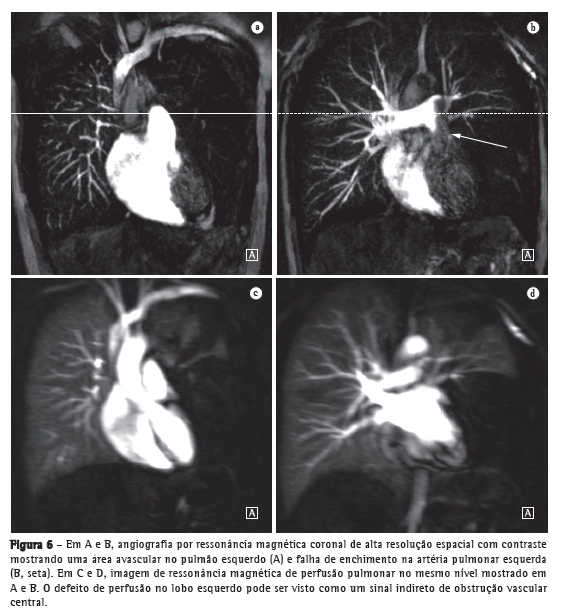

Avanços técnicos substanciais em angio-RM pulmonar foram introduzidos nos últimos anos (Figuras 5 e 6). Novas melhorias estão em andamento; dentre elas, o uso de imagens paralelas, compartilhamento de visão, angiografia do tipo time-resolved echo-shared(17-19) e perfusão pulmonar. Essas técnicas encurtaram o tempo de aquisição da angio-RM, tornaram-na menos suscetível a artefatos de movimento e melhoraram a resolução espacial. Um estudo mostrou que um protocolo combinado de RM (progressão de RM em tempo real para RM de perfusão, e desta para angio-RM) é confiável e sensível, produzindo resultados semelhantes aos obtidos com TC com multidetectores de 16 fileiras.(18)

Hipertensão pulmonarO uso da RM permite uma avaliação abrangente da hipertensão pulmonar, sendo que a angio-RM e sequências de perfusão permitem a identificação e diferenciação de embolia pulmonar e outras entidades.(22,23) Além disso, a angio-RM permite uma avaliação detalhada da localização do material tromboembólico e, para o planejamento cirúrgico, a angio-RM é tão útil quanto a angiografia por subtração digital e a angiografia por TC.(24,25) Na RM, as sequências de perfusão podem ser avaliadas quantitativamente, o que permite que a gravidade da doença de pequenos vasos seja avaliada. A redução da perfusão correlaciona-se com a gravidade da doença, e resultados preliminares sugerem que a perfusão é um substituto sensível para o monitoramento da doença.(4) Imagens estruturais do pulmão permitirão a exclusão de doenças do parênquima pulmonar. Medidas de fluxo sanguíneo e pressão cardíaca direita permitem que se estimem a pressão arterial pulmonar e o esforço cardíaco e facilitam a identificação de doença valvular concomitante.